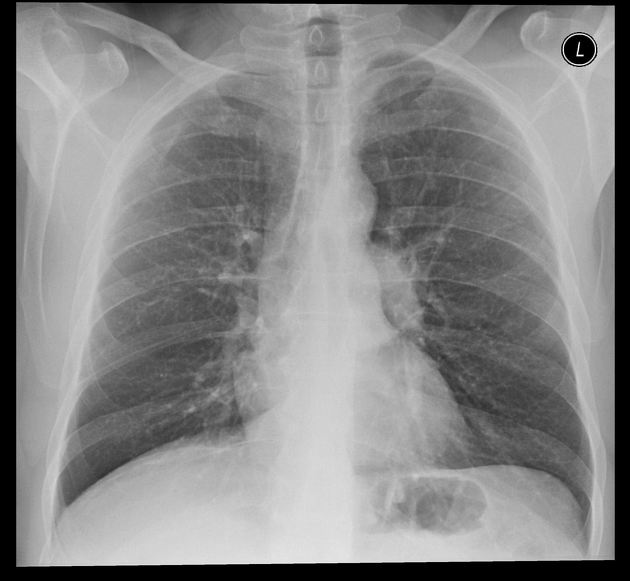

Example 1

Take a look at the following example. Let us go through how we would systematically analyse this and the diagnosis.

D – This is a Chest X-Ray taken on ….., of the following patient….. Is there a previous CXR to compare to

R – Commenting first on the quality, it is not rotated, there is adequate inspiration, the projection is posterior-anterior and it is adequately exposed as I can see the vertebral bodies clearly

“On initial inspection, there appears to be increased opacification in the right middle lobe, but I will proceed to go through it systematically.”

A – Starting with the airways, the trachea is not deviated, and the carina is visible.

B – The pleural markings go all the way to the costal margin so there is no evidence of a pneumothorax. Going through the lung zones, there is increased opacification in the right middle lobe compared to the left. This opacification does not follow the contours of a lobe and has well defined edges, suggesting that it may be a mass.

C – The heart is not enlarged and the borders are visible.

D – The hemidiaphragms are clearly visible and there is no blunting of the costophrenic angles. There is no free air under the diaphragm.

E – There are no foreign objects or bone fractures.

There is no abnormality in the review areas, including the apices, behind the heart

In summary the key finding is an opacification in the left hilar region, which is suggestive of a mass.

Lung Cancer